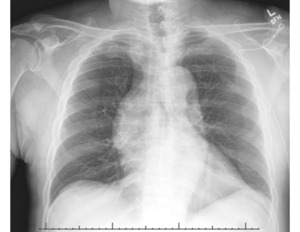

However, upon further careful medical history taking, the patient also reported chest pain that started that morning. He stated that the pain was located over the left side of his chest, felt sharp, was intermittent, but not worsened with exertion. He denied any recent upper respiratory infection, trauma to the chest, history of drug use, or previous history of chest pain.6 Although his blood pressure and heart rate were mildly elevated, his cardiac examination was normal, and he had good pulses in all of his extremities. We ordered tests to assess for potential acute coronary syndrome including electrocardiograms (ECG), high sensitivity troponins, and chest radiography. The ECG (Figure 2) showed sinus tachycardia at about 102 beats per minute, poor R wave progression across the precordial leads suggestive in this case of previous anteroseptal injury, and left ventricular hypertrophy per the modified Cornell criteria, but no ST segment elevations concerning for acute cardiac ischemia. The high-sensitivity troponin was very minimally elevated to 0.07 and downtrended to 0.06 three hours later. All other labs were grossly unremarkable besides mildly elevated liver function tests. The portable chest radiograph, however, showed a modestly widened superior mediastinum, as pictured in Figure 3. We quickly proceeded with a bedside ultrasound which showed a large ascending aortic aneurysm (Figure 4) with an associated proximal aortic dissection. In Figure 5, a dissection flap can be clearly visualized. After consulting with cardiothoracic surgery while starting the patient on an esmolol drip for blood pressure and impulse control, we obtained a CT angiogram of the chest which showed a 7.7 cm dissecting aneurysm involving the ascending aorta and proximal aortic arch with a large, partially thrombosed false lumen and extension into the proximal innominate artery (Figure 6). The radiologist also noted there was marked compression of the superior vena cava (SVC) due to the large aneurysm of the ascending aorta. The patient later required a nicardipine drip after high-dose esmolol failed to optimally control his hyperdynamic state.